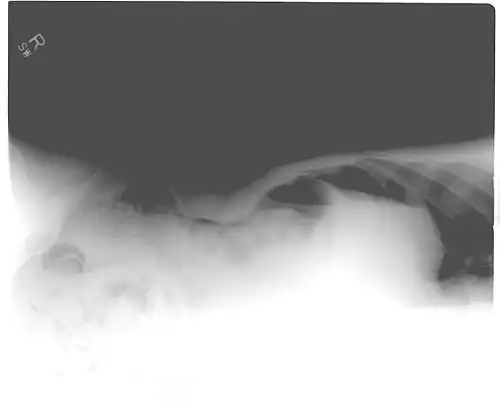

Signs that can be seen on projectional radiography are shown below:

Another pneumoperitoneum on chest X-ray. -

Pneumoperitoneum seen on X-ray with the patient lying on his left side. -